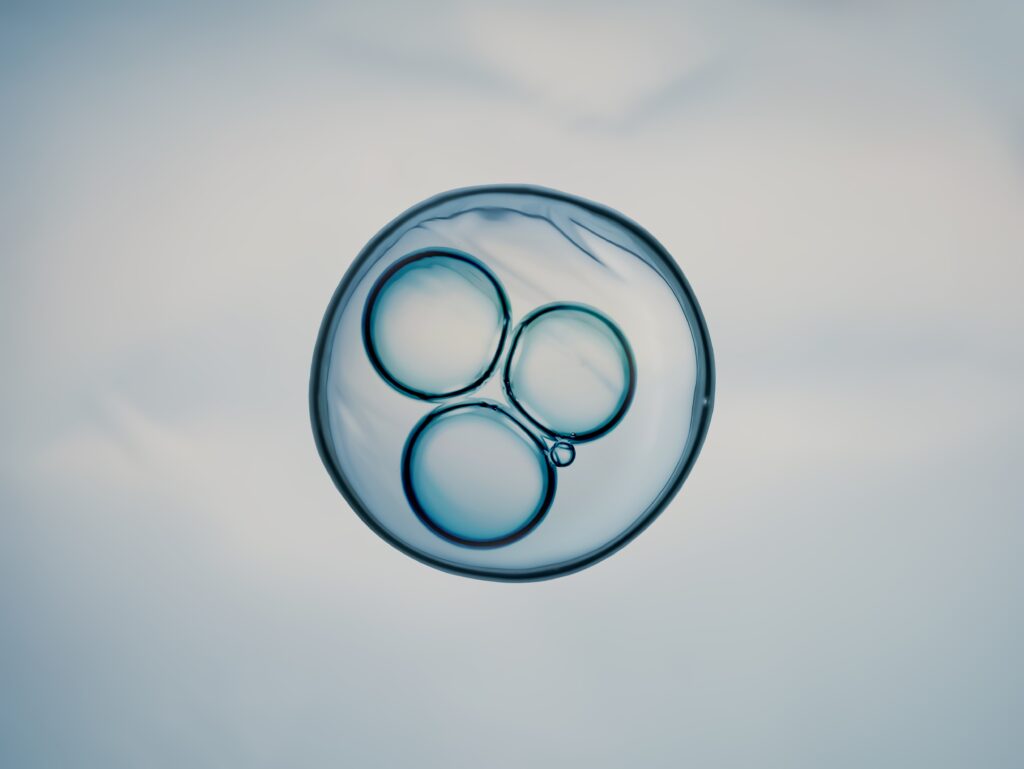

By fertilising the reconstructed eggs and activating them with a compound called roscovitine, the team triggered chromosome reduction. However, the process was not fully accurate: the chromosomes often segregated incorrectly, leading to embryos with abnormal genetic make-up. Out of 82 eggs created, fewer than 10% developed to the early embryo stage, and none were grown beyond six days.